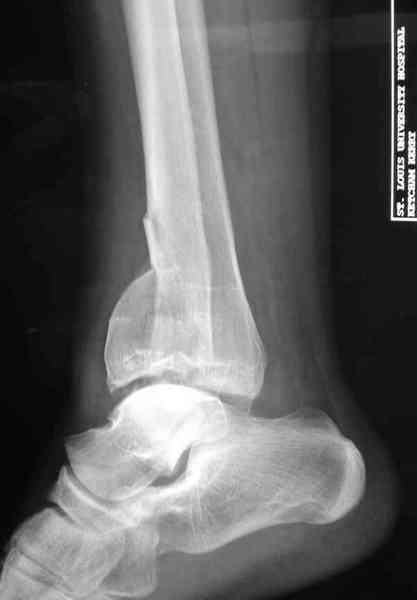

Добавлены КТ снимки. Прошу прощения за качество.

С уважением, Коваленко А.Н.